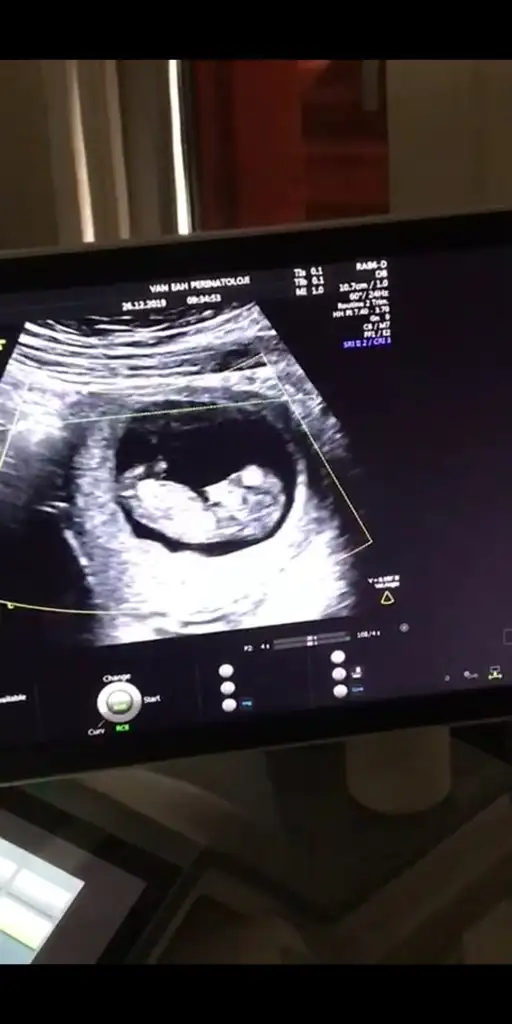

12 haftalık görüntü lütfen cinsiyet tahmini yapar mısınız

• Screenshot_20191227-194320.webp

Screenshot_20191227-194320.webp

20,4 KB · Görüntüleme: 46